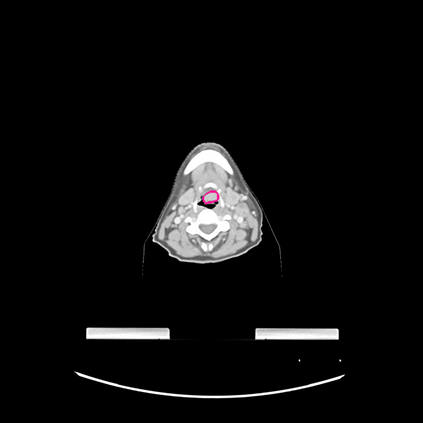

Radiomics uses quantitative medical imaging features to predict clinical outcomes. Currently, in a new clinical application, finding the optimal radiomics method out of the wide range of available options has to be done manually through a heuristic trial-and-error process. In this study we propose a framework for automatically optimizing the construction of radiomics workflows per application. To this end, we formulate radiomics as a modular workflow and include a large collection of common algorithms for each component. To optimize the workflow per application, we employ automated machine learning using a random search and ensembling. We evaluate our method in twelve different clinical applications, resulting in the following area under the curves: 1) liposarcoma (0.83); 2) desmoid-type fibromatosis (0.82); 3) primary liver tumors (0.80); 4) gastrointestinal stromal tumors (0.77); 5) colorectal liver metastases (0.61); 6) melanoma metastases (0.45); 7) hepatocellular carcinoma (0.75); 8) mesenteric fibrosis (0.80); 9) prostate cancer (0.72); 10) glioma (0.71); 11) Alzheimer's disease (0.87); and 12) head and neck cancer (0.84). We show that our framework has a competitive performance compared human experts, outperforms a radiomics baseline, and performs similar or superior to Bayesian optimization and more advanced ensemble approaches. Concluding, our method fully automatically optimizes the construction of radiomics workflows, thereby streamlining the search for radiomics biomarkers in new applications. To facilitate reproducibility and future research, we publicly release six datasets, the software implementation of our framework, and the code to reproduce this study.

翻译:放射科使用定量医学成像特征来预测临床结果。目前,在一个新的临床应用中,通过一个超常试验和高压过程,通过人工操作,从广泛的现有选项中找到最佳放射法。在本研究中,我们提议了一个框架,自动优化每个应用程序的放射工作流程的建设。为此,我们将放射作为模块工作流程,并包括每个部件的大量通用算法。为了优化每个应用程序的工作流程,我们使用随机搜索和聚合的自动机学习方法。我们用12种不同的临床应用来评估我们的方法,结果在曲线下应用的以下领域:1) 脂色瘤(0.83);2) 脱氧型纤维瘤(0.82);3 初级肝脏肿瘤(0.80);4 气肠肿瘤(0.77)、5 彩虹肝脏移植(0.61); 6 脑膜细胞变异常(0.45); 7) 肝细胞变异常(0.8) 脑纤维变异位(0.80); 9) 直径直线型癌症(0.74) 和头型癌症(0.77) 直径研究(10) 。